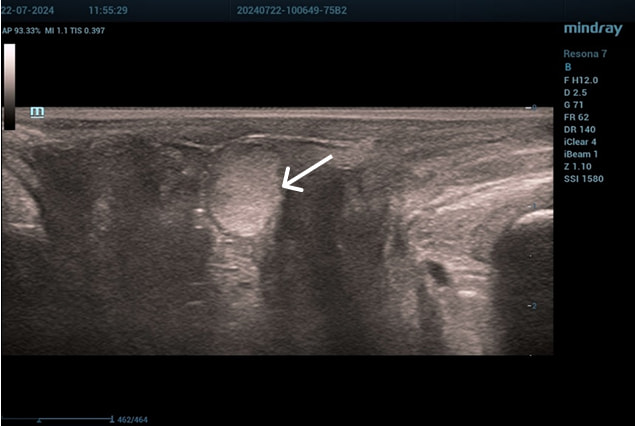

Эхограммы периуретральной области

Трансперинеальный доступ, линейный датчик.

Слева от уретры округлое образование с четкой капсулой и мелкодисперсной взвесью размерами 1,5×1,0 см (филлер с воспалением), справа — анэхогенное овоидное образование (филлер).

Эхограмма 1

Эхограмма 2